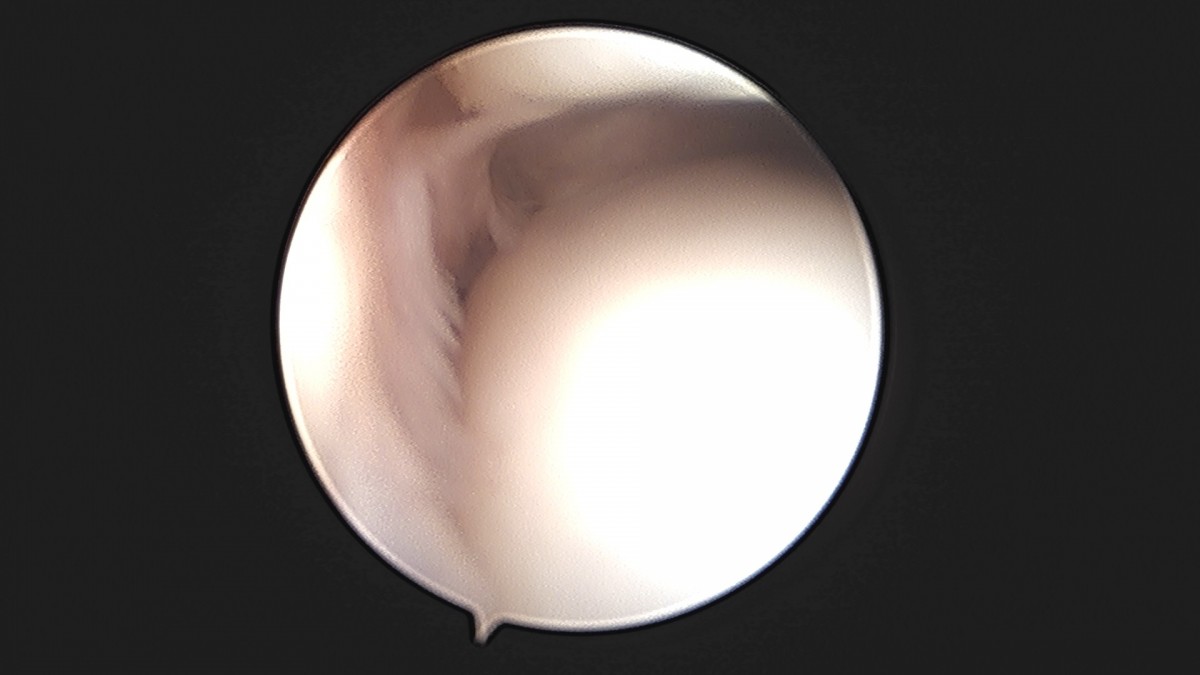

이재상원장님 발목 활액막 절제술 및 인대 봉합술 이승O 환자

작성자 최고관리자 댓글 0건 조회 787회 작성일 25-09-16 15:24